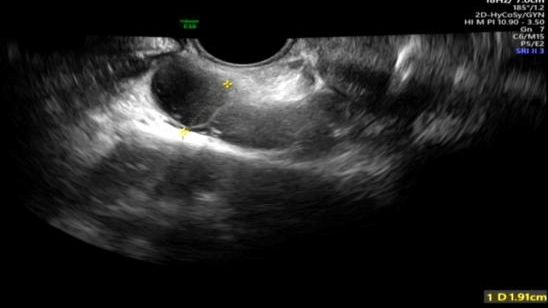

正常清晰显示双侧宫颈及输卵管

正常宫腔